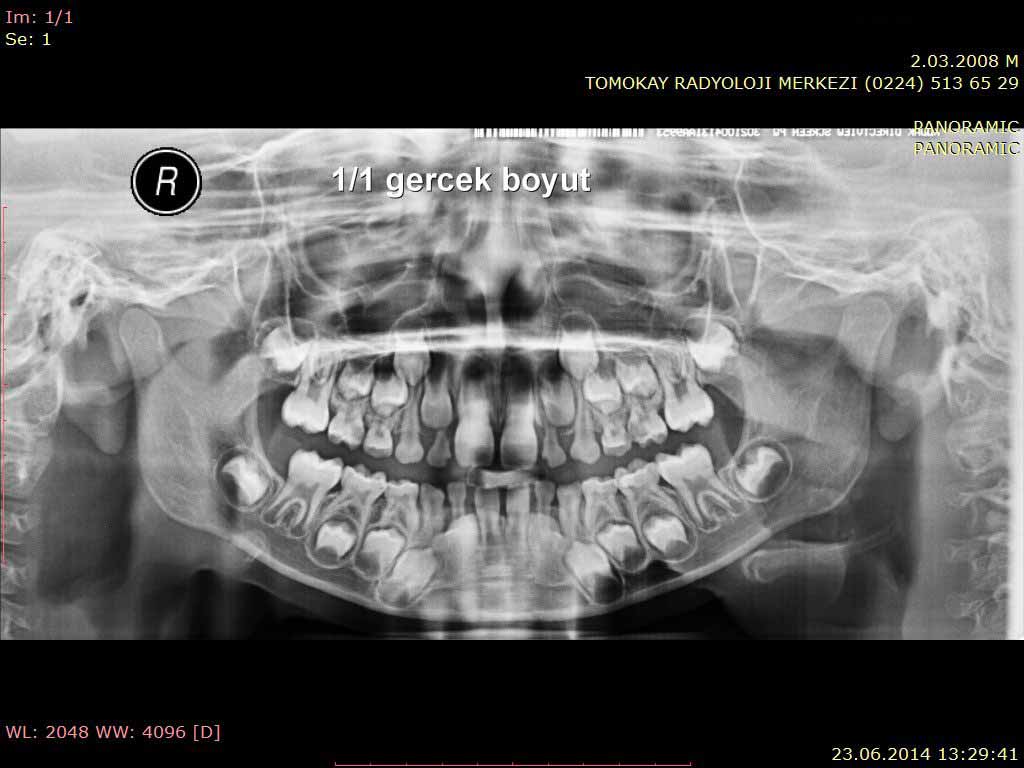

ما هو تصوير اشعة البانوراما للأسنان؟

يوفر إمكانية رؤية البنية التشريحية للأسنان والفكين في فيلم واحد على مستوى ثنائي الأبعاد.